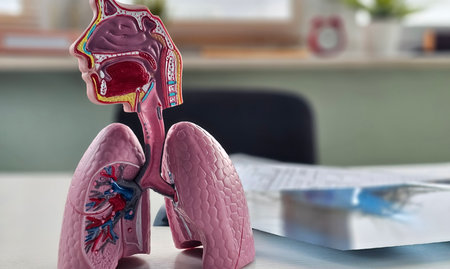

Anatomical model of human lungs featuring vivid colors and intricate patterns, highlighting the complexity of the respiratory system in an educational display.

Medical model of human respiratory system displayed during consultation with doctor in clinic

Human respiratory system showing lungs and trachea placed on a desk near educational materials